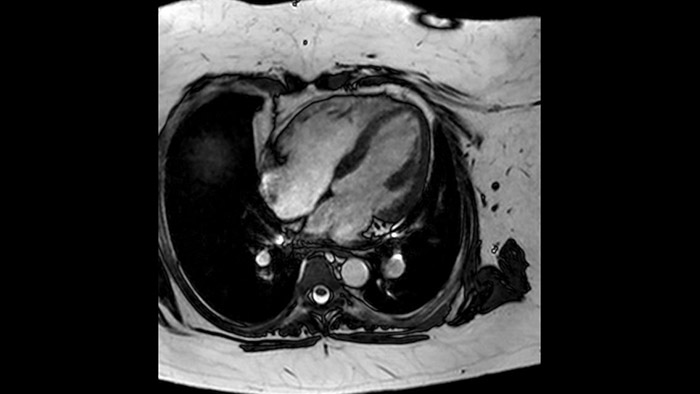

Comprehensive cardiac MR imaging

Diagnostic and prognostic utility of cardiac MR is increasing. Assess the anatomy and function of the heart using cine acquisitions, acquire information about perfusion and viability of the cardiac tissue, visualise potential edema with black blood sequence, access and even quantify tissue characterisation with CardiacQuant.